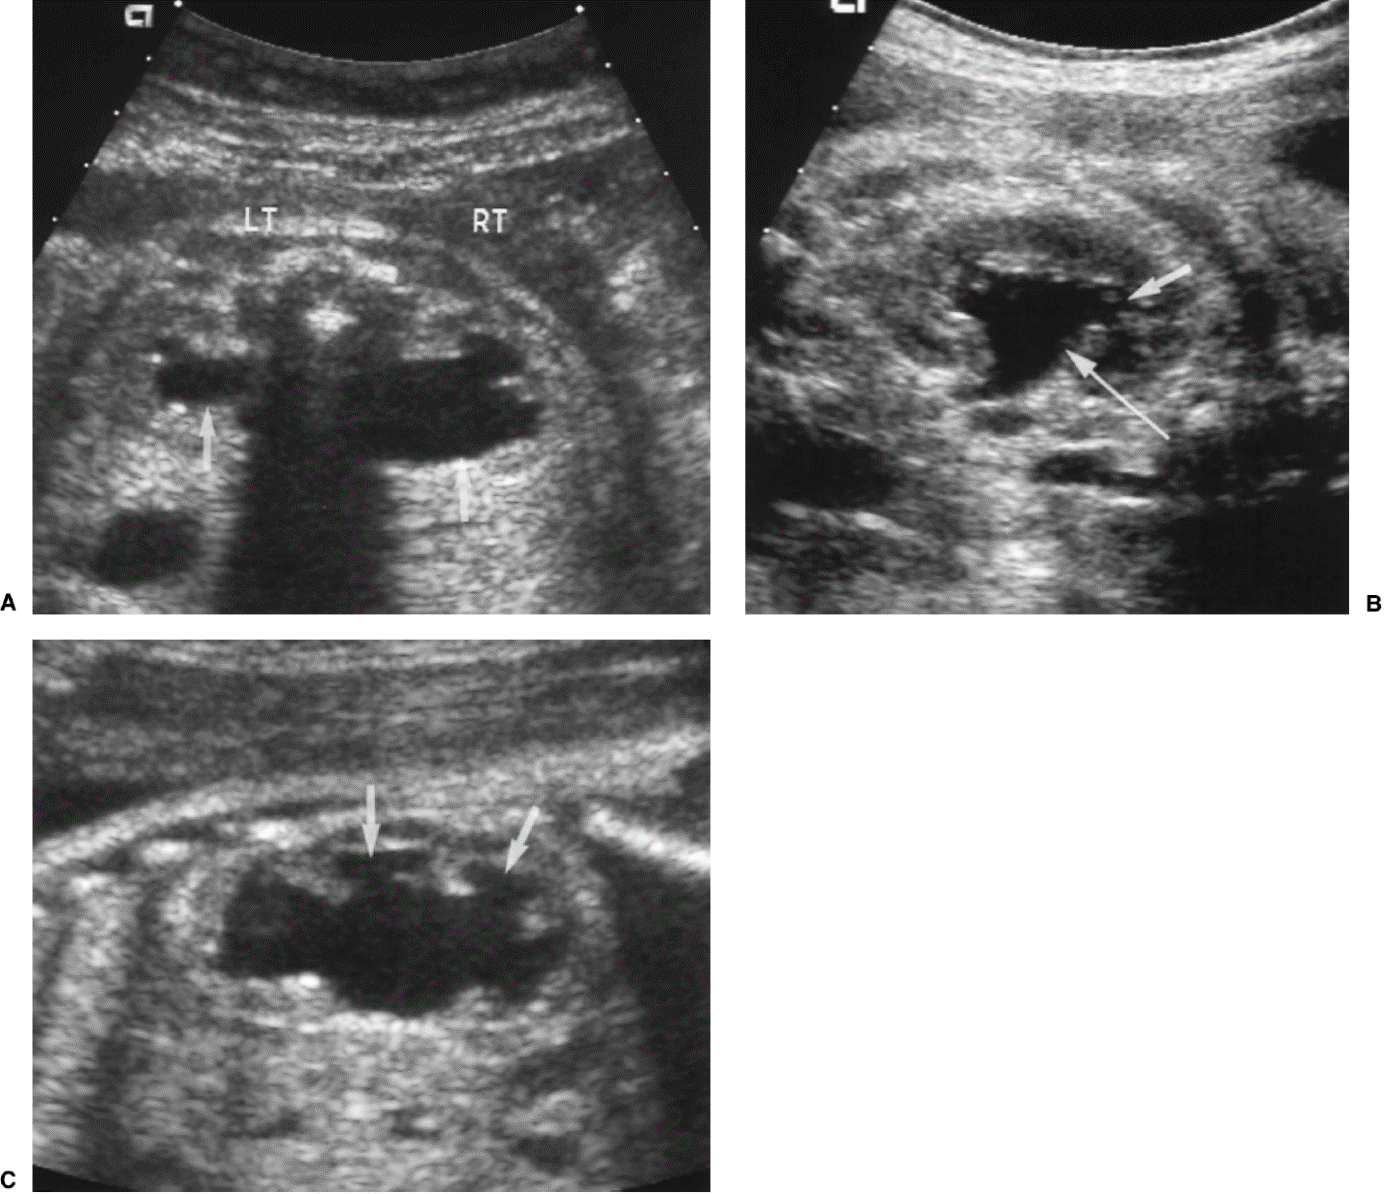

Links normale situatie: 1 nier, 2 nierbekken, 3 urineleider, 4 blaas, 5 overgang van urineleider in blaas, 6 plasbuis.

Rechts situatie zoals die bij urethrakleppen kan ontstaan: Verwijding van de nieren, het nierbekken en de urineleider. De urineleider wordt niet alleen wijder in de breedte maar ook in de lengte zodat en geslingerd verloop ontstaat. De blaas is zeer gespierd geworden en daardoor dikwandig en kartelig. De blaasuitgang is ook zeer gespierd en daardoor vernauwd. Het eerste deel van de plasbuis is verwijd tot aan de urethrakleppen. De blauwe pijl wijst naar de plaats van de urethrakleppen. Door de gespierde blaaswand wordt de urineleider die links in het plaatje zichtbaar is (dat is aan de rechter zijde van het kind) vernauwd waardoor de urineleider stroomopwaarts nóg meer verwijding vertoont. Aan de rechter zijde is de klep tussen urineleider en blaas beschadigd geraakt. De inmonding van de urineleider in de blaas is een wijde opening waardoor urine direct weer vanuit de blaas naar de nier kan stromen (Groene pijl)